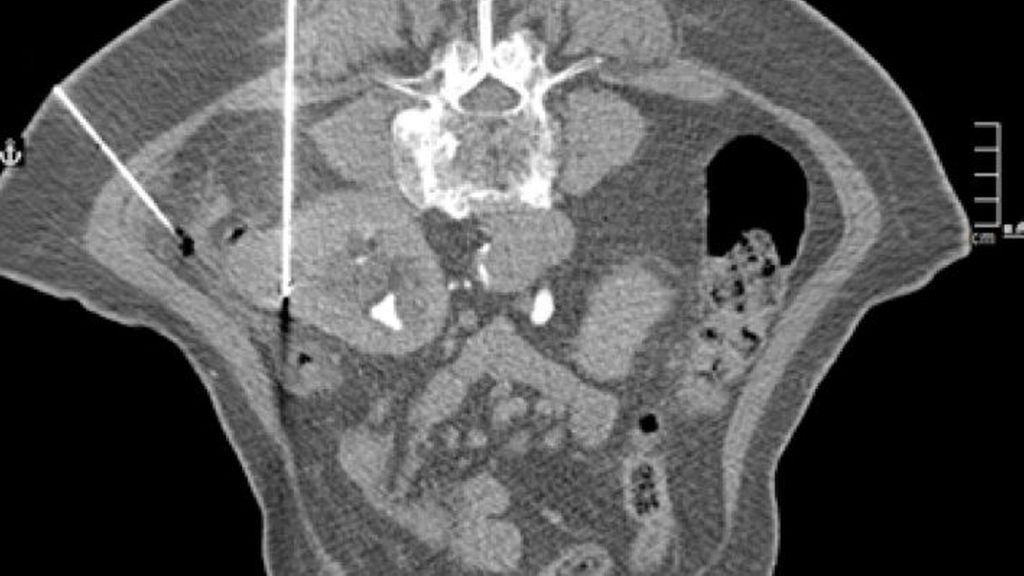

In Österreich sind ablative Verfahren der Niere Domäne der interventionellen Radiologie. Der Eingriff erfolgt in der Regel unter stationären Bedingungen. In den Nierentumor wird CT-gezielt eine oder mehrere Sonden eingebracht (Abb. 1–4), die durch Aktivierung die Temperaturdifferenz und somit das Absterben des Tumors bewirkt. Mit einer anschließenden CT-Untersuchung lässt sich der Effekt der Ablation bestätigen.

Die allermeisten ablativen Interventionen bei Nierentumoren erfolgen perkutan. Alternativ besteht auch die Möglichkeit des laparoskopischen bzw. offenen Zugangs mit Freilegung des Tumors und laparoskopischem bzw. offenem (Abb. 5–8) Einbringen der Sonde. Bei der Frage des Zugangs ist abgesehen von der lokalen Expertise die Lage des Tumors relevant. Ist der Tumor perkutan nicht bzw. schwer erreichbar, wie zum Beispiel bei einer Transplantatniere, bietet die Laparoskopie bzw. die offene Freilegung eine Alternative.